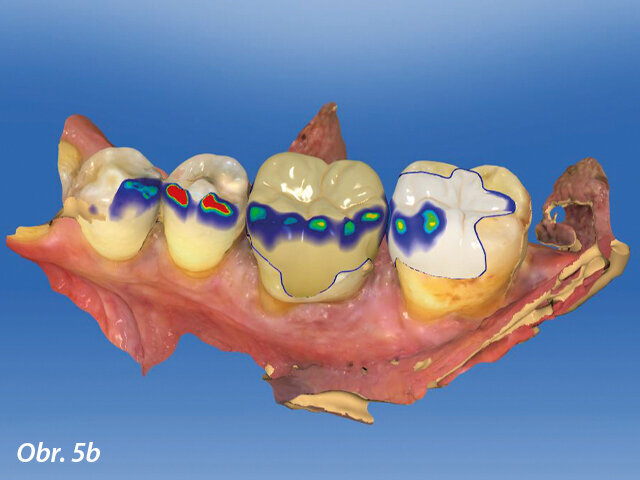

CAD výroba v dolní čelisti.

Pomocí intraorálního skeneru byly získány digitální otisky situace. Aby se zabránilo zrcadlovým snímkům nebo nežádoucím odrazům, byly zuby nejprve co nejdůkladněji osušeny. Následovala registrace skusu (sken) a import dat do CAD softwaru. Skeny byly zkontrolovány a byly z nich odstraněny artefakty. Po výpočtu virtuálního modelu a sestavení čelistí podle registrace skusu bylo snadné, pomocí několika kliknutí, vyznačit hranice preparace a osu nasazení náhrady. Při konstruování náhrad byl cennou pomůckou automatický biogenerický software pro počáteční navrhování. Na prvotních návrzích byly provedeny pouze minimální změny. Konstrukce náhrad trvala jen velmi krátkou dobu (obr. 4, 5) a poté byla data přenesena do CAM přístroje. V náhledu pro frézování byl naposledy zkontrolován design náhrad, například hodnoty pod minimální tloušťkou stěn.